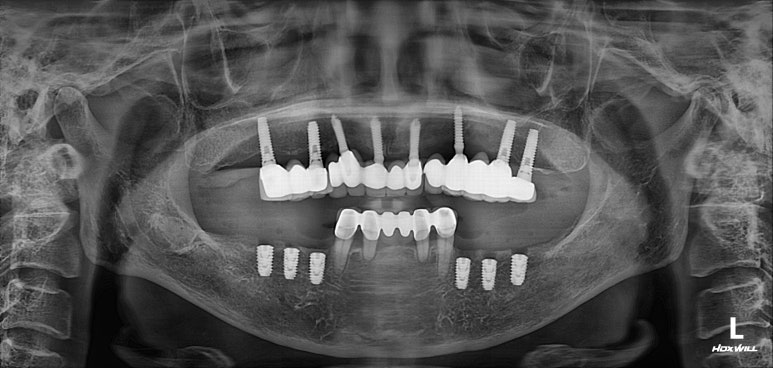

위턱은 임플란트로 어느 정도 치아 자리가 채워져 있는 모습이지만, 아래턱은 어금니가 상당히 많이 없네요.

임플란트로 모두 치료해보기로 하였습니다.

빠르고 정확한 수술을 위해 네비게이션 임플란트 계획합니다.

수술 후 촬영한 치과용 파노라마 사진에서, 정~말 깔끔하고 예쁘게 식립된 임플란트를 보실 수 있습니다.

아래턱뼈 내부에는 하치조신경이라는 감각신경이 주행하고 있는데요, 네비게이션 임플란트를 통해 수술 후 감각마비 없이 깔끔하게 마무리 되었습니다.

치과용 파노라마 사진을 보면 뭔가 좌우 대칭으로 깔끔하게 완성된 아래턱 양쪽 어금니 임플란트를 보실 수 있어요!!

치과용 파노라마 엑스레이만 보아도, 임플란트 여섯개가 깔끔하게 제작된 것을 보실 수 있을겁니다.